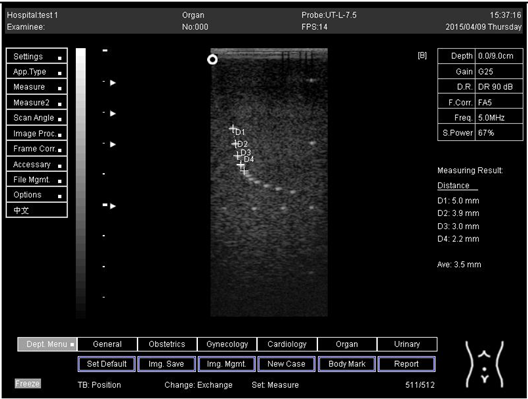

6.0 Axial resolution

Biomimetics 07 00130 i013

D1 = 3.0

D2 = 2.0

D3 = 1.0

D4 = 0.6

6.0Lateral resolution

Biomimetics 07 00130 i014